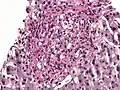

PAS diastase showing Histoplasma in a liver biopsy.

PAS diastase stain